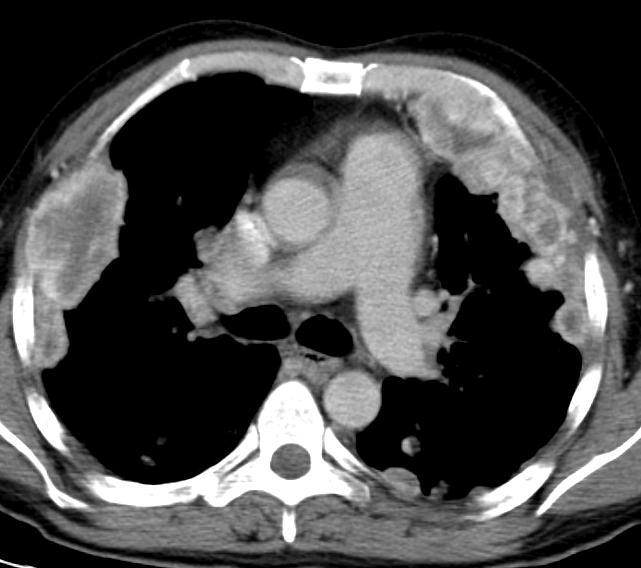

Gallery Pleural renal mets

renal mets